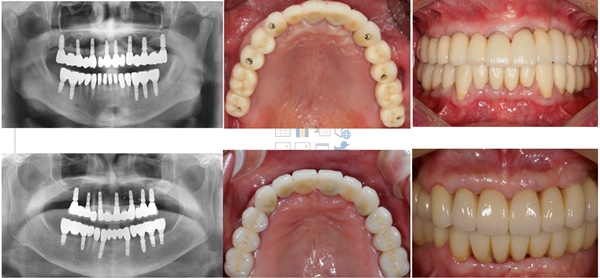

임플란트란 치아가 상실되었을 때 사용 가능한 치아 보철물로 자연치아의 90~95%의 기능으로 사용이 가능하다고 해요. 특수금속으로 만들어진 인공치아를 상실된 치아 부위의 잇몸뼈에 식립하고 그 위에 인공치아를 장착해 수복하는 치료방법으로 본래 자기 치아와 가장 유사한 형태와 기능을 한다고 해요.

임플란트는 관리만 잘하게되면 평생쓸 수 있다는 말이 있을 만큼 수명이 길다고 해요. 그리고 치아 브릿지처럼 인접한 치아를 삭제하지않아도 되므로 남은 치아를 보호할 수 있어요. 가장 큰 장점은 씹는 힘이 자연치아와 유사해 씹는 기능이 증진되며 심미적 안정으로 대인관계나 생활에 자신감을 가질 수 있다고 해요.

우선 CT촬영 등을 통해 구강상태를 정밀 진단 후 환자의 상태에 따라 맞는 치료 계획을 세웁니다. 구체적인 임플란트 시술 과정과 기간은 환자의 상태에 따라 달라질 수 있다고 해요.

4단계 크라운제작 및 교정

수술부위가 아물면 임플란트 지주대와 주변치아를 본을 뜬뒤, 치아 형태의 보철물인 크라운 제작을 한다고 해요. 크라운 제작 기간은 보통 일주일 정도라고 해요. 보철물이 완성되면 크라운을 임플란트 지대주에 장착해 고정시킵니다고 해요. 그 다음 음식을 씹을 때 불편함이 없도록 조정한다고 해요.